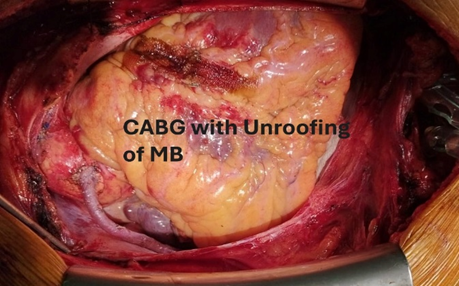

The patient was denied to do Intravascular Ultrasound (IVUS) and Fractional Flow Reserve (FFR) assessment. So, after evaluation of the patient, he was sent to the operating room for coronary artery bypass surgery with unroofing of myocardial bridge in mid LAD. Surgery was performed with endotracheal intubation under G/A and with median sternotomy. After median sternotomy, pericardiotomy was done. Aorta showed healthy, PA (Pulmonary Artery) showed mildly tense, LV-Normal. Cardiopulmonary Bypass was established with aortic and dual stage venous cannulation. At first on pump beating heart, RSVG (Reverse saphenous venous graft) to PDA, distal grafting was done with prolene 7/0.

Then aorta was cross clamped and heart was arrested with antegrade cold-blood cardioplegia. After that to inspect epicardial surface of heart for intramyocardial LAD, was easily detected. Epicardial incision was given over the normal site of LAD coronary artery with 15 size surgical blade. Then dissection was extended proximally into the bridging portion of LAD coronary artery with the dissection of epicardial fat and underlying muscle or myocardial bridge with the help of Potts scissors and Electrocautery. The length of the myocardial bridge was about 4.5 cm. Careful dissection was done to avoid damage to the LAD coronary artery and its branches such as diagonal artery and to avoid injury to right ventricle. During dissection of epicardial fat and outer part of myocardial bridge electrocautery or Liga clip were used for hemostatic purpose.

Figure 9: Surgical Unroofing of Myocardial Bridge with exposed LAD artery.

Figure 11: After completion of procedure.

To reduce and/or manage any bleeding (venous or muscular) from both sides of the myotomy edges, we employed over-and-over eversion sutures with 6/0 prolene, when patient was under cardiopulmonary bypass with full heparinization. The aortic cross clamp was removed. Proximal anastomosis was done on aorta with 6/0 prolene using side biting clamp. The patient was gradually weaned from cardiopulmonary bypass. After decannulation, heparin was reversed. After maintaining proper hemostasis, wound was closed in layers keeping two mediastinal drain tubes in situ. Patient was shifted to Cardiothoracic ICU with stable hemodynamic. He was extubated on 1st post-operative day and subsequent post-operative period was uneventful. Echocardiography was done on 1st post operative day showed preserved biventricular function. Patient was discharged from the hospital on the 7th day after surgery.

Myocardial bridge is a congenital malformation on the affected coronary artery. It is associated with several cardiovascular problems, including myocardial ischemia, heart attack, arrhythmia, even sudden cardiac arrest, and death. Surgical unroofing with coronary artery bypass grafting is a safe and effective treatment for symptomatic isolated myocardial bridge and or concomitant with other coronary artery disease where other options are failed, to improve coronary perfusion, relieve myocardial ischemia and improve the quality of life of the patients by relieving the compression of tunneled artery.